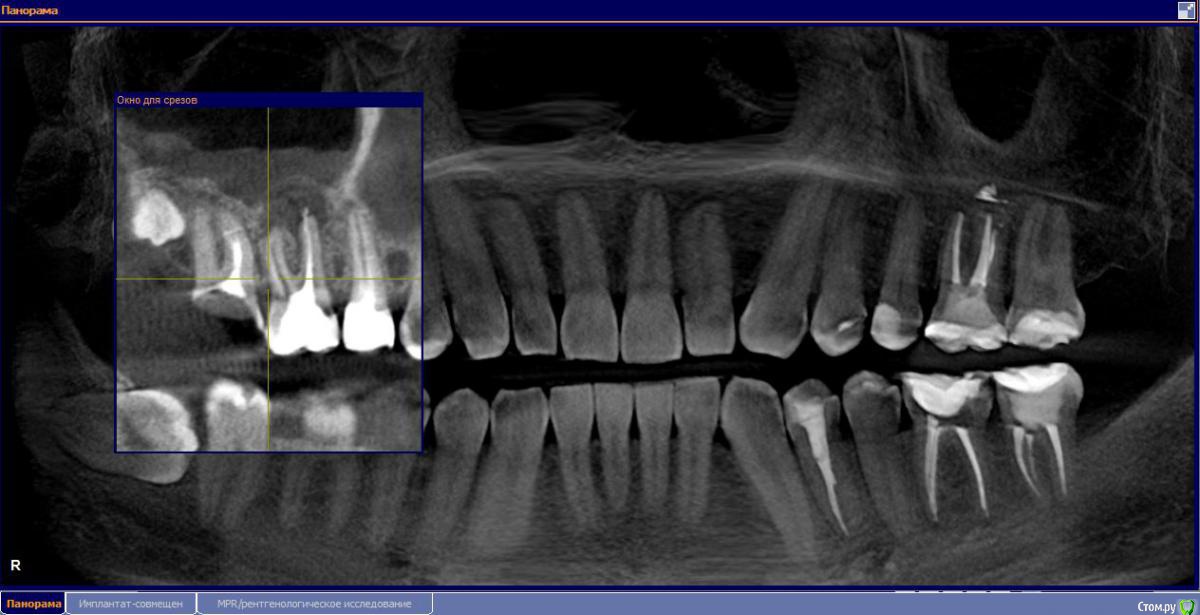

М, 33 года. Есть показания к одновременному удалению 16-го зуба - киста, и 17-го - разрушена верхушка. 8-й предлагают оставить, чтобы "держал кость" (как то так мне озвучили).

Через 3-4 месяца рекомендуют синус-лифтинг и установку двух имплантатов.

- Возможно ли консервативное перелечивание 16 зуба и есть ли смысл?

- Насколько опасная имеется киста?

и 6 и 7й зубы не выглядят 100% кандидатами на удаление.

1.6 большая вероятность сохранить,но понятнее при очном осмотре и диагностическом вскрытии. 1.7,скорее всего,не жилец,но тоже очно взглянуть на него стОит